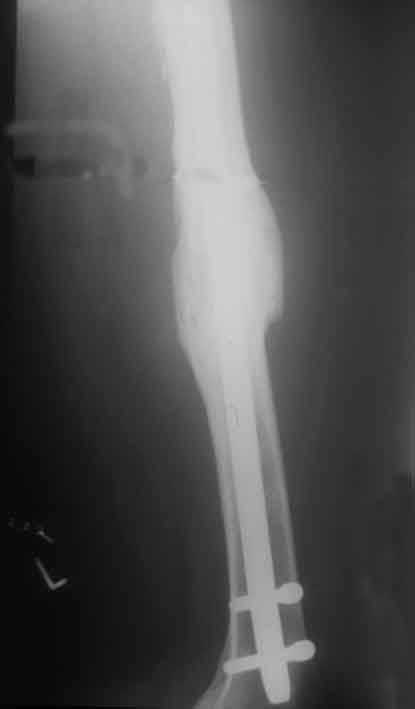

Achsengerecht verheilte Fraktur ein Jahr nach dem Unfall mit gutem Callus als Zeichen dynamischer Frakturheilung.